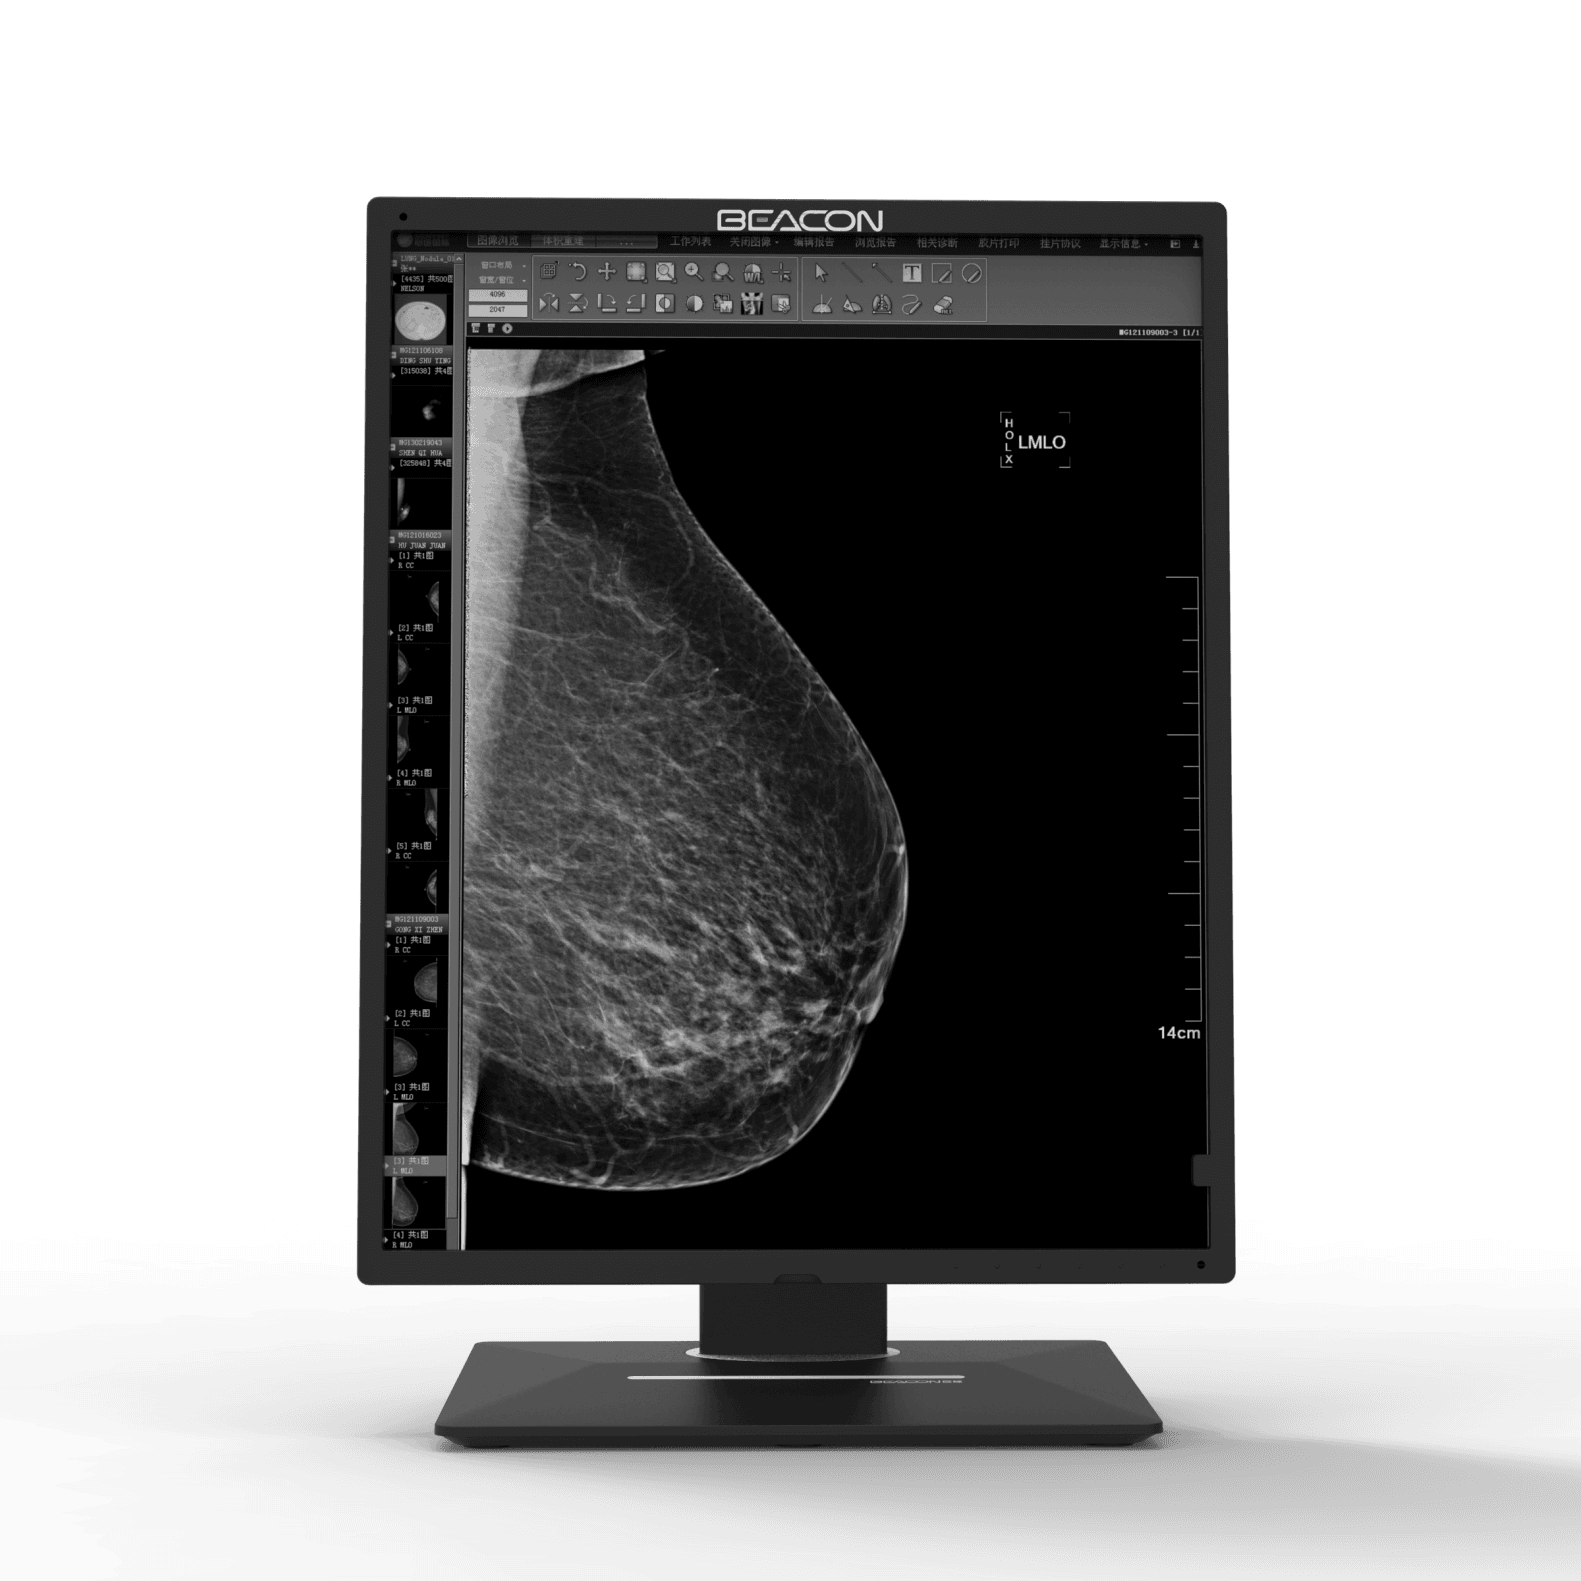

C510S tiene funciones de imagen en color y escala de grises, 5 millones de píxeles de resolución ultra alta, brillo ultra alto, contraste ultra alto, amplio ángulo de visión y bajo consumo de energía. Puede ser ampliamente utilizado en varios equipos de imágenes médicas incluyendo mama digital y sistema de PACS.

Las imágenes médicas, incluyendo los detalles más sutiles, se pueden visualizar con precisión. Mantener la coherencia de visualización entre diferentes pantallas, así como la visualización y las diferentes modalidades de imágenes, garantizar la precisión del diagnóstico.

Pantalla de diagnóstico

Pantalla de diagnóstico